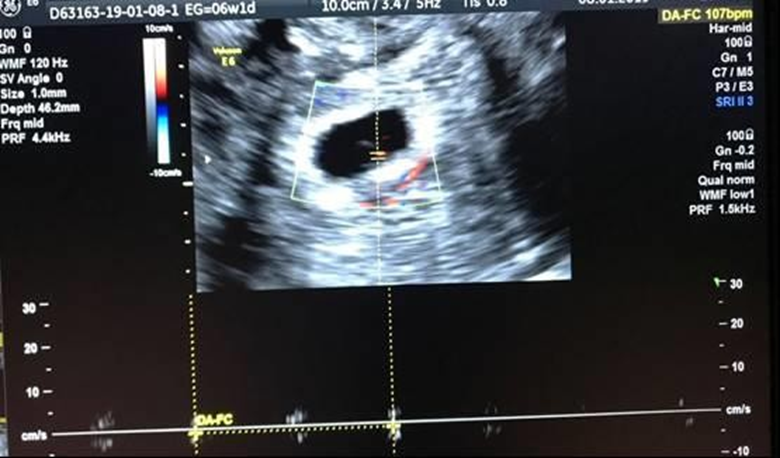

After completing the two courses of UPA, the patient came to the medical consultation for control visit, reporting an 8-week course secondary amenorrhea . A pregnancy test was performed, being positive. A transvaginal ultrasound showing a gestational sac in situ with an embryo inside with a crown-rump length (CRL) of 4.2 mm corresponding to 6W + 1D and positive Fetal Heart Rate (FHR) quantified at 107x´(Figure 2). It was concluded that the patient presented spontaneous ovulation approximately 2 weeks after finishing the treatment

Figure 2. Positive Fetal Heart Rate